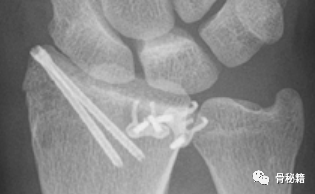

掌侧勾钢板固定骨折块

还有一些相应的内固定设计,专门诊断此类边缘骨折